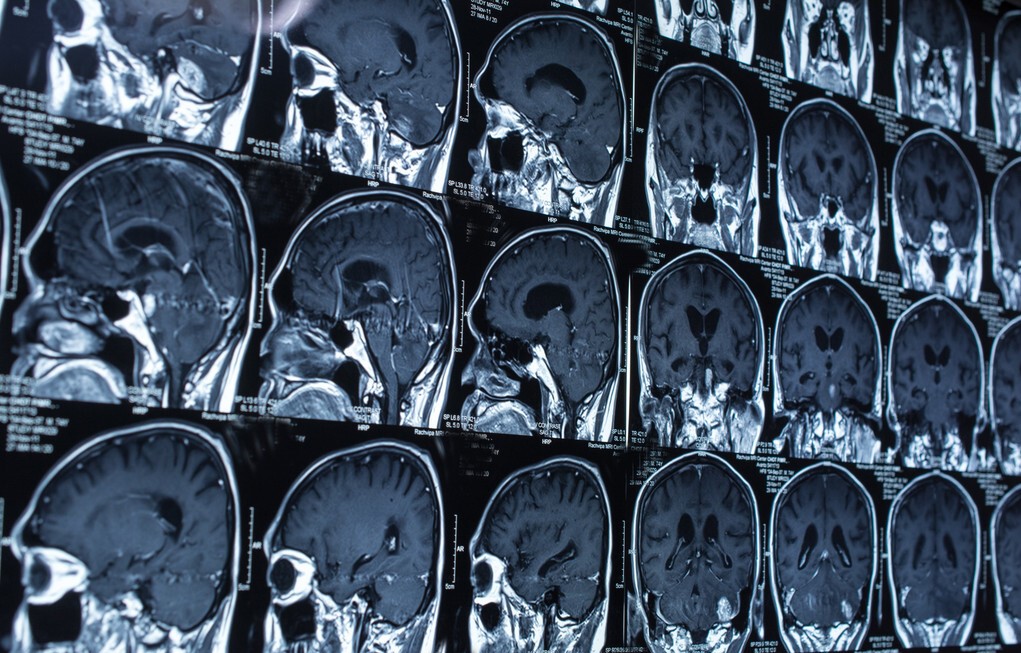

腔隙性脑梗塞,是一种影像学的描述性术语。它指的是,在影像学检查中,发现了大脑中存在着类似脑梗塞病灶一样的“空洞”,但是非常的微小,大多数只有几个毫米大,与真正的脑梗塞不一样。